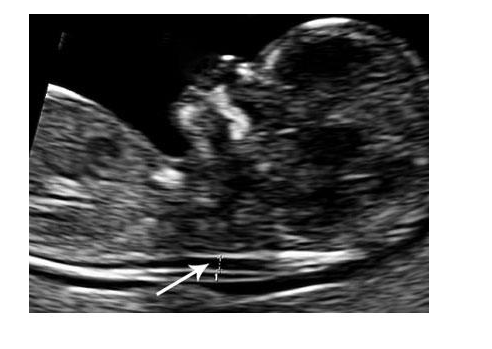

Ο φλεβώδης πόρος είναι ένα μικρό αγγείο που συνδέει την ομφαλική φλέβα με την κάτω κοίλη φλέβα και μεταφέρει αίμα πλούσιο σε οξυγόνο στον εγκέφαλο του εμβρύου. Συνήθως κλείνει λίγα λεπτά μετά την γέννηση. Η εκτίμηση της αιματικής ροής στο φλεβώδη πόρο βασίζεται στην εμφάνιση του κύματος α, αν είναι δηλαδή θετικό (φυσιολογικό) ή ανάστροφο (παθολογικό). Η αναστροφή του κύματος α σχετίζεται με αυξημένο κίνδυνο για χρωμοσωμικές και καρδιακές ανωμαλίες. Αναστροφή κύματος α σε κυήσεις 11-14 εβδομάδων εμφανίζεται σε έμβρυα με ευπλοειδία στο 3% ενώ σε έμβρυα με χρωμοσωμικές ανωμαλίες στο 55-65%.

Ο φλεβώδης πόρος

και ποια η σημασία του